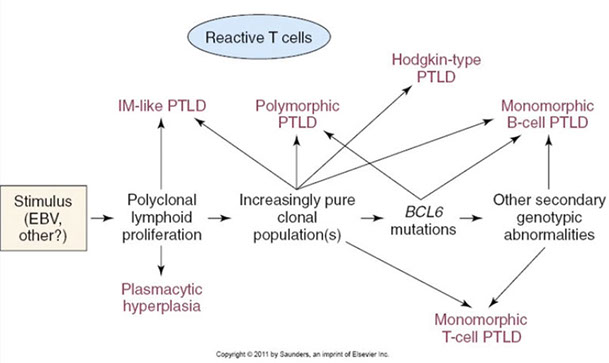

- 1/3 of pts disease free for 10 yrs, but usually progresses to MM in 2-3 years

-Adverse px factors are osteopenia and low levels of other Igs, which suggest occult myeloma

plasmacytoma of rib [14]

Solitary Plasmacytoma with Minimal BM Involvement

Diagnostic criteria:

- Biopsy proven solitary lesion of clonal plasma cells

- normal imaging (skeletal survey, MRI or CT) except for the lesion in question

- No CRAB or amyloidosis